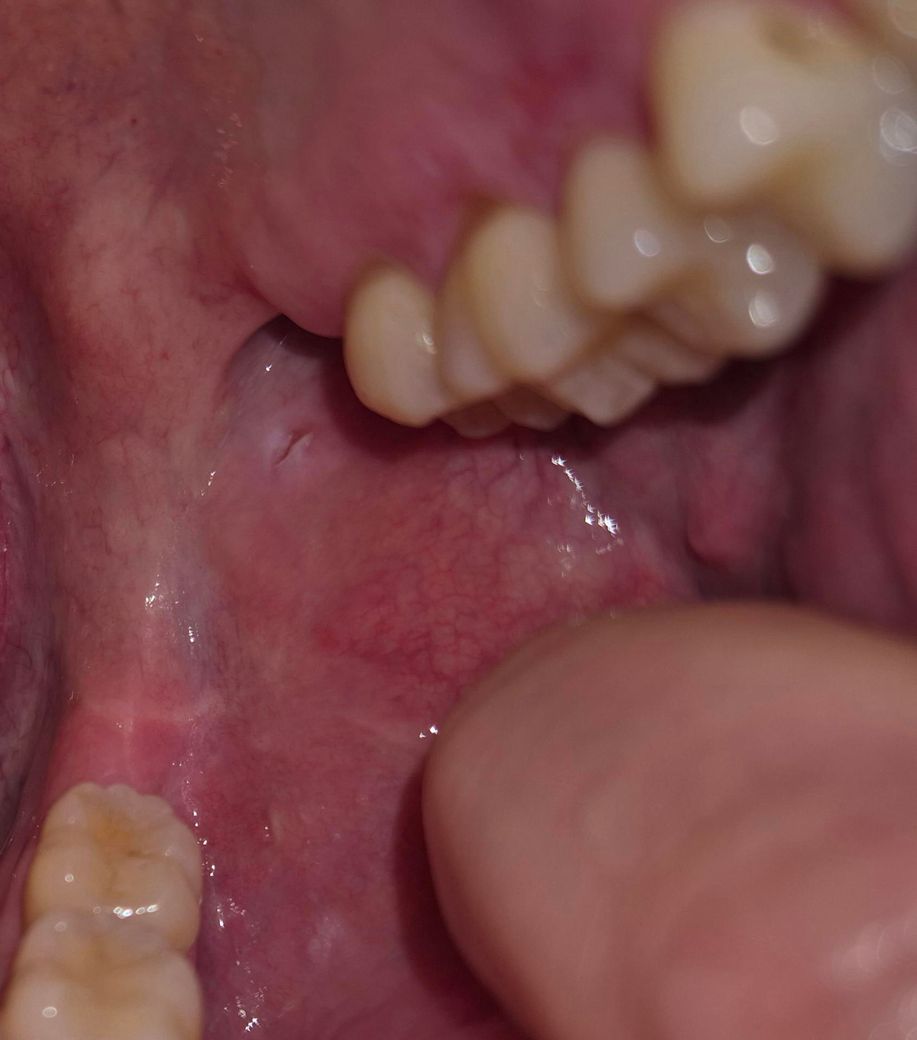

오래 지속되면 구강암이될 가능성이 있다는데 일단 사진 첨부합니다.

• 2번 째 사진

말씀 주신 경과와 기저질환을 종합하면 단순 재발성 구내염로만 보기에는 주의가 필요합니다.

볼 안쪽 점막 병변이 6주 이상 지속되고 크기나 모양 변화 없이 아물지 않는 경우, 감별해야 할 범주는 크게 세 가지입니다. 첫째, 만성 외상성 궤양입니다. 씹힘, 날카로운 치아, 교정물, 이를 악무는 습관 등 반복적 자극이 원인이며 통증이 거의 없을 수 있습니다. 둘째, 면역조절제 관련 점막 병변입니다. 휴미라(adalimumab)는 종양괴사인자 억제제로, 감염에 대한 국소 면역 반응을 약화시켜 구강 궤양의 장기 지속, 진균·바이러스 감염, 비특이적 염증 병변이 오래 가는 경우가 있습니다. 셋째, 비교적 드물지만 반드시 배제해야 할 구강 편평상피암 또는 전암성 병변입니다. 통증이 없고, 단단하게 만져지거나, 가장자리가 불규칙하거나, 2주에서 3주 이상 치유 경향이 없는 경우에는 조직학적 확인이 원칙입니다.

현재처럼 1달 반에서 2달 지속되었고, 면역억제제 사용 중이며, 최근 수술 병력까지 있는 경우라면 “경과 관찰” 단계는 이미 지났다고 보는 것이 보수적입니다. 구강암으로 바로 단정할 근거는 부족하지만, 배제를 위해서는 조직검사가 필요할 수 있습니다.

진료과 선택은 이비인후과 또는 구강악안면외과가 적절합니다. 일반 치과보다는 구강 점막 병변 평가와 필요 시 생검이 가능한 곳이 좋습니다. 이비인후과에서도 구강 점막 병변에 대한 진찰과 조직검사가 가능합니다. 방문 시 휴미라 사용 중이라는 점과 병변 지속 기간을 반드시 말씀하시는 것이 중요합니다.

정리하면, 통증이 없더라도 6주 이상 지속되는 구강 점막 병변은 정상 소견으로 보지 않으며, 특히 종양괴사인자 억제제 사용 환자에서는 조기 평가와 필요 시 조직검사가 권고됩니다. 빠른 시일 내 이비인후과 또는 구강악안면외과 진료를 권합니다.

• 사진의 소견 및 이야기 하신 내용만 놓고 심각한 소견일 가능성이 높아 보이거나 하지는 않습니다만 구내염이 지속되는 것이 길어진다면 한 번 평가를 받아보는 것이 안전하긴 하겠습니다. 관련하여서는 일차적으로는 이비인후과로 가는 것이 가장 적절할 것으로 사료됩니다.